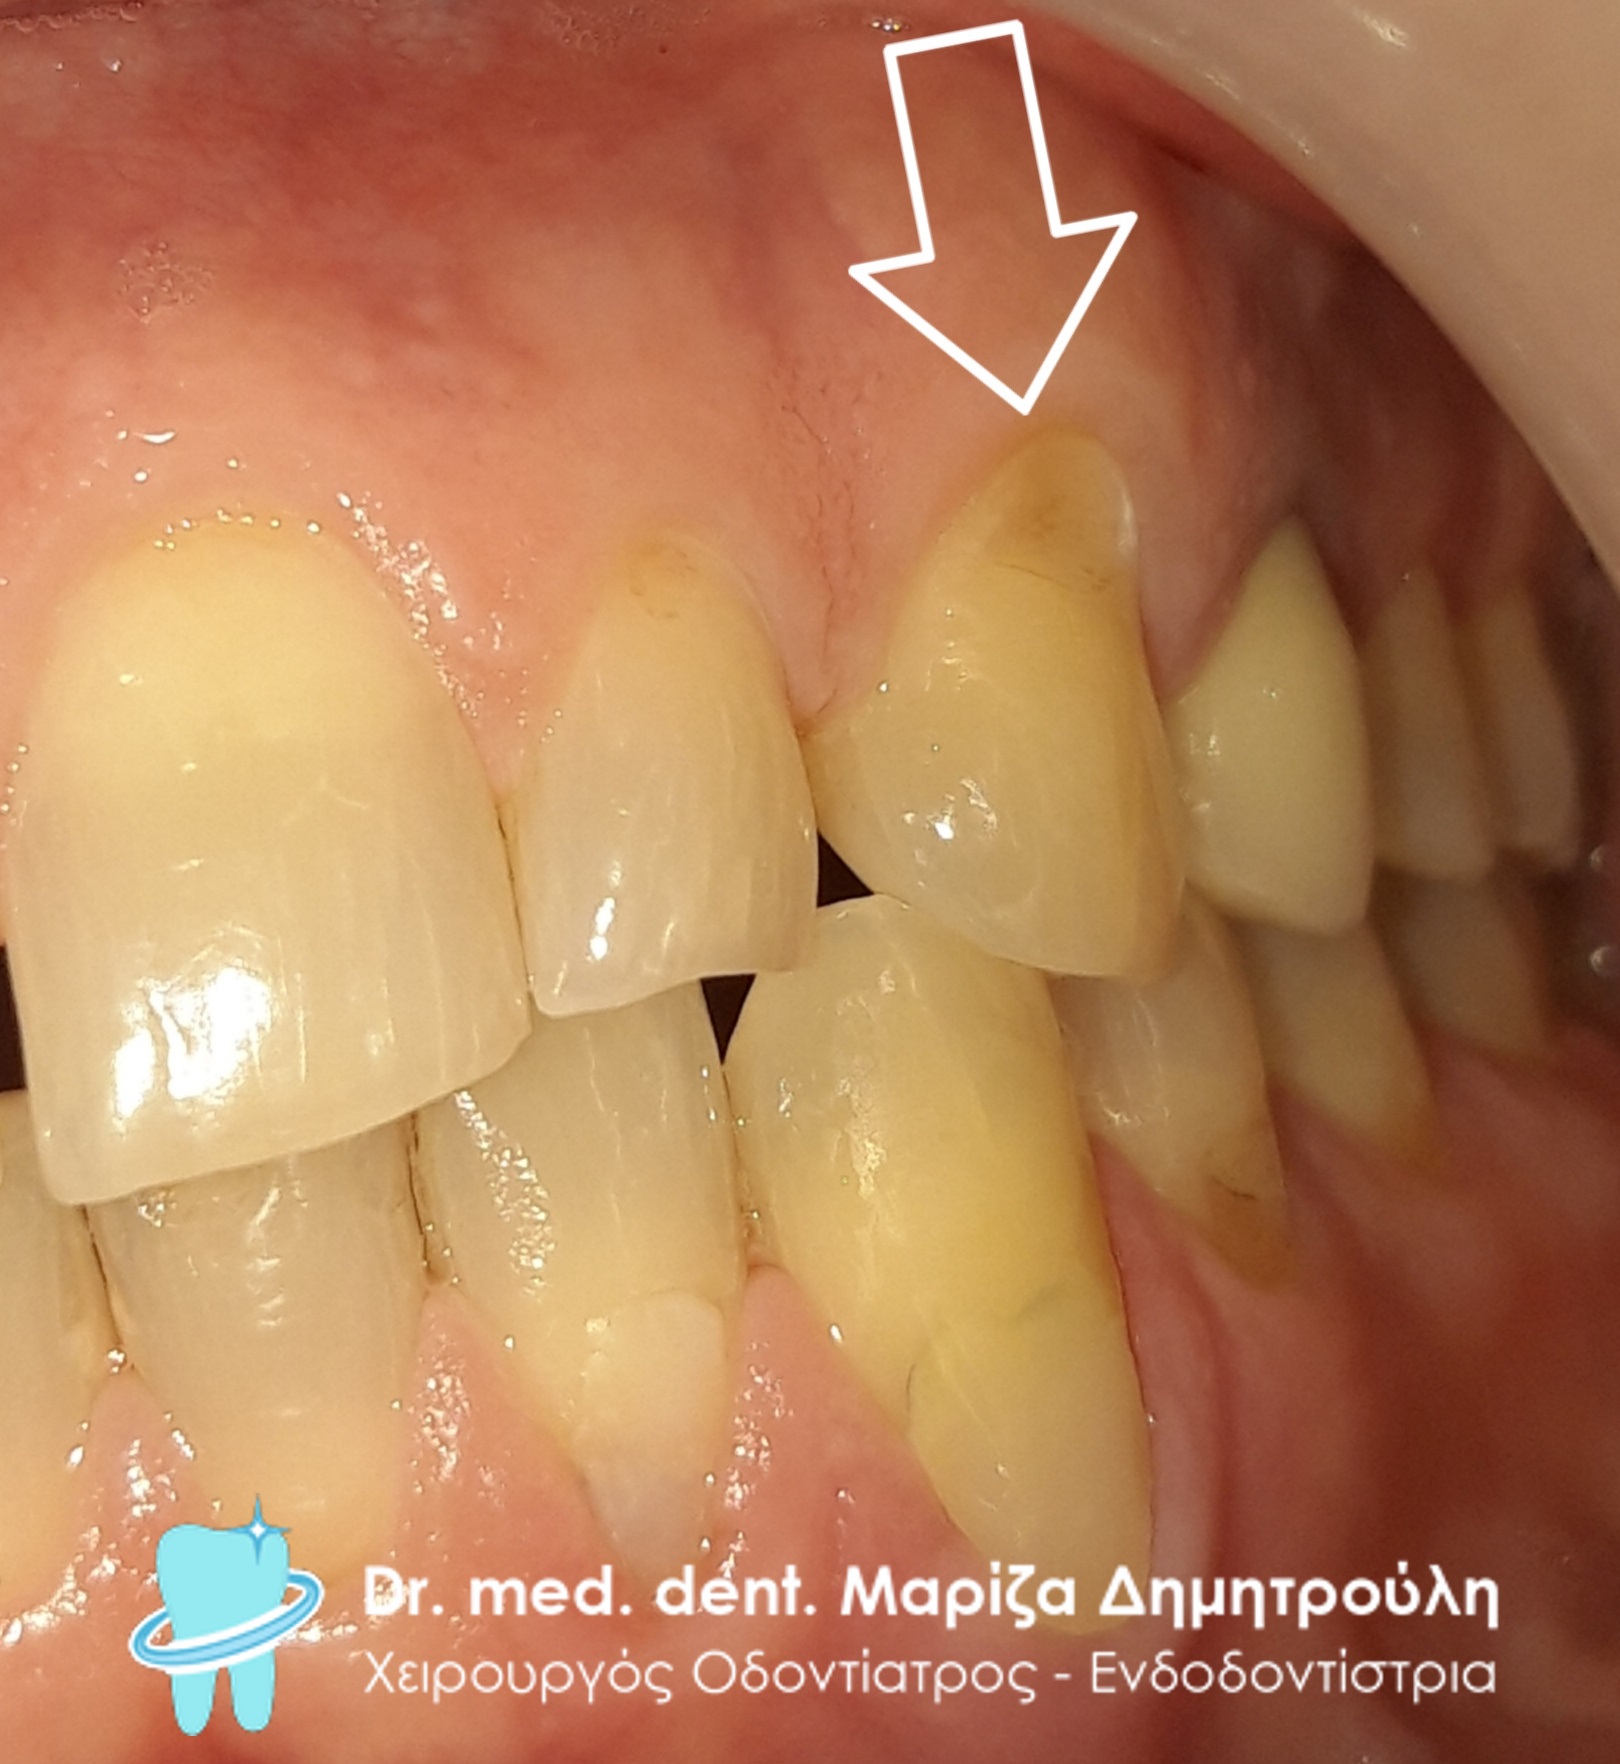

Ο ασθενής επισκέφτηκε το ιατρείο γιατί αισθανόταν μία ενόχληση / πόνο σε κάποιο δόντι του στην αριστερή πλευρά της άνω γνάθου κατά τη λήψη κρύων τροφών και ποτών. Η κλινική εξέταση αποκάλυψε μία αλλοίωση στον αριστερό κυνόδοντα της άνω γνάθου. Η αποκατάσταση της βλάβης πραγματοποιήθηκε με λευκό σφράγισμα ρητίνης.

ΠΡΙΝ

META